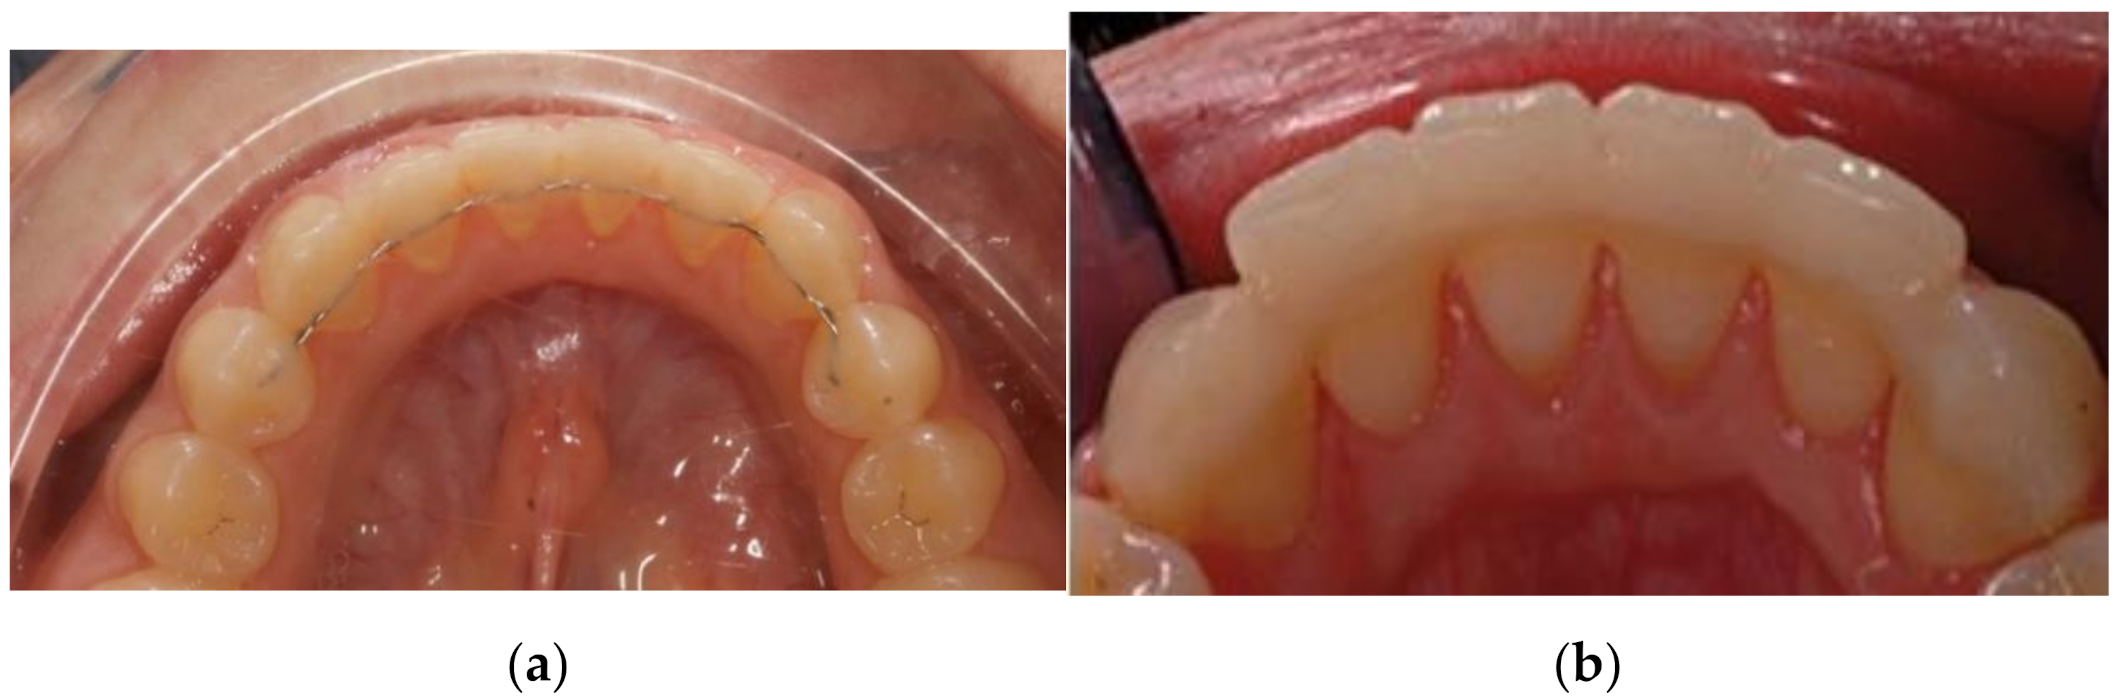

2. Experimental Section